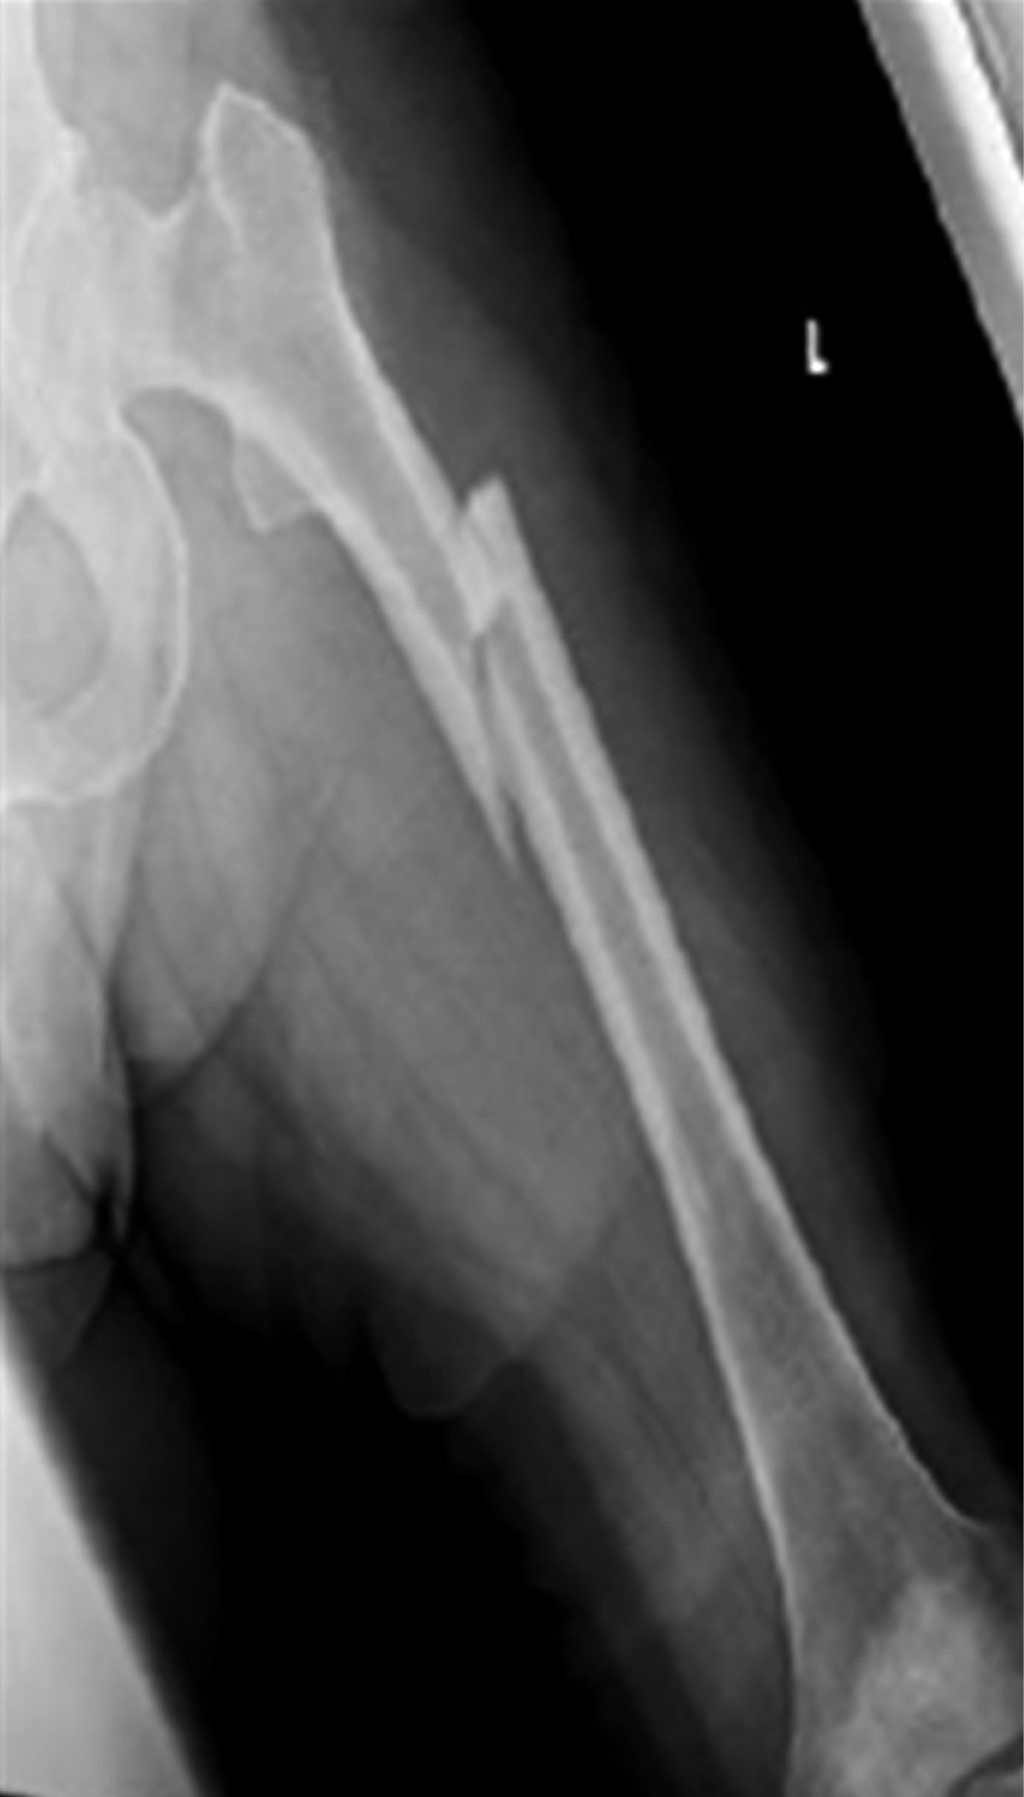

A 76-year-old female patient used alendronate for four consecutive years, switching afterward to zoledronic acid and using it for five more years, making it a total of nine years of BISPH use. She arrived at the emergency room after experiencing a spontaneous fracture of the left femur while taking a walk (Figure 3), leading to a fall from her height. The clinical examination and radiographs demonstrated a left Atypical Femur Fracture (AFF). Upon further observation, an incomplete fracture was found in the right femur (Figure 4). She underwent a first surgical intervention, and two days later, a second one; intramedullary nailing was performed in both femurs (Figure 5). A lumbar spine dual-energy X-ray absorptiometry (DEXA) was performed, which reported a T Score of −0.9, spine TBS of 1.382, left femoral neck T-score of −1.5, and right femoral neck T-score of −1.7, leading to an osteopenia diagnosis.

The patient progressed favorably; she was prescribed physical therapy and began using a walker. BISPH therapy was immediately suspended and replaced with Teriparatide, calcium supplements, and vitamin D. Due to clinical improvement, the patient was discharged from the Orthopedics Unit.

Figure 5